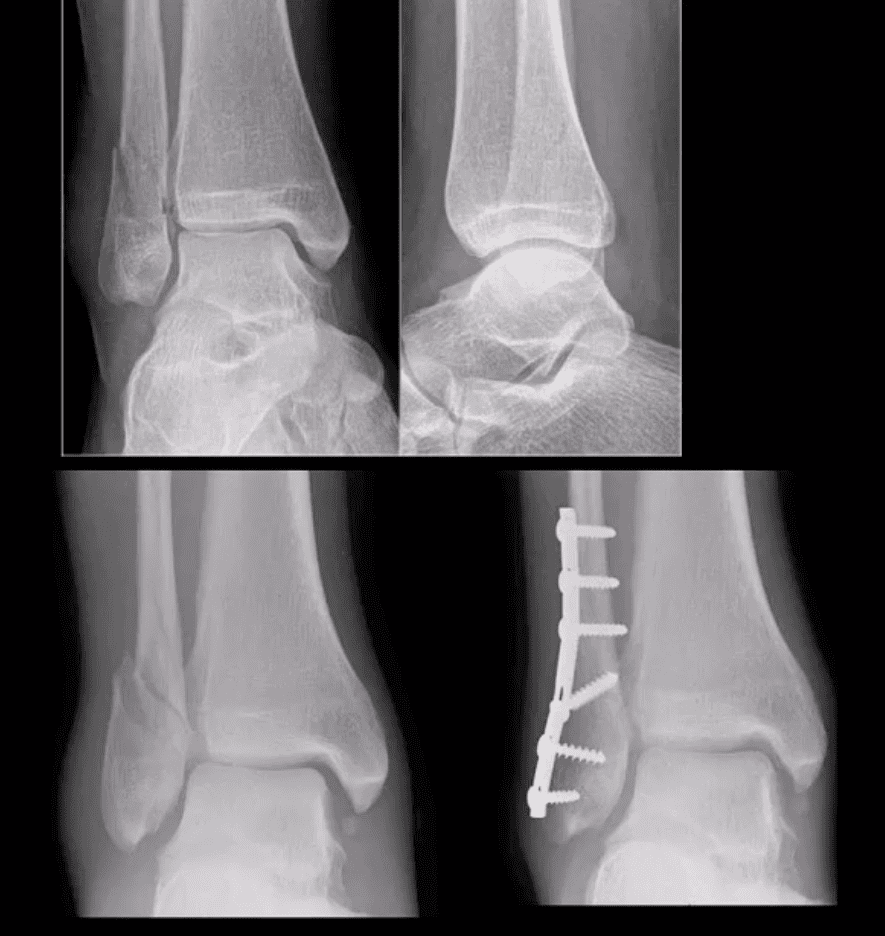

Weber B at Level of Syndesmosis

- Can be stable or unstable. On occasions, the decision is made during operative exploration.

- CT scanning may help with further evaluation

- Management: depends on stability. Additional stabilization required if syndesmosis is ruptured

Bimalleolar & Trimalleolar Fx

- Above top images Bimalleolar Fx v. unstable, result of pronation and abduction/external rotation. Rx: ORIF.

- Trimalleolar Fx: 3-parts ankle Fx. Medial and lateral malleolus and avulsion of theposterior aspect of tibial plafond. More unstable. Rx: operative